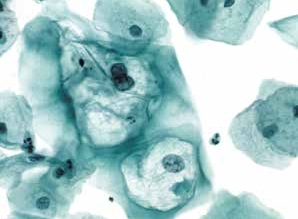

图4-70 非角化型鳞癌(高倍、液基、巴氏染色)

癌细胞片状排列,异型性明显,肿瘤素质清晰可见。液基制片坏死物聚集在癌细胞周围,称“黏附的肿瘤素质”。传统涂片肿瘤素质一般分布在背景中。